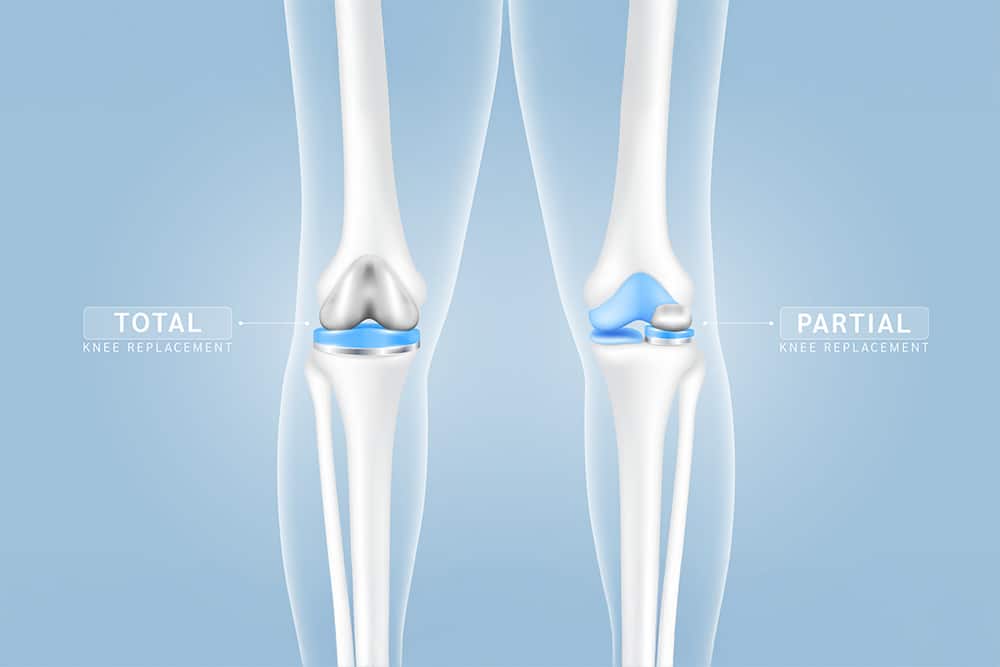

In Singapore, the two main orthopaedic surgical options are partial and total knee replacement, and the choice usually depends on whether the damage is confined to one compartment or affects multiple areas of the knee. Because these procedures involve different surgical scopes, the general recovery timeline, hospital stay, and overall costs can differ as well. Key differences between the two include:

If you’re looking up “partial vs full knee replacement” online, it’s most likely due to the fact that a total knee replacement procedure has been suggested and you’re trying to confirm whether it’s even necessary. The clearest difference is scope. A partial knee replacement treats one damaged compartment, while a total knee replacement replaces most or all of the joint surfaces. Because the partial approach is more targeted, more natural bone and supporting structures are preserved, including key ligaments when intact. For suitable patients, this usually translates into a knee that feels more natural during daily movement, as more of the original joint mechanics are preserved.